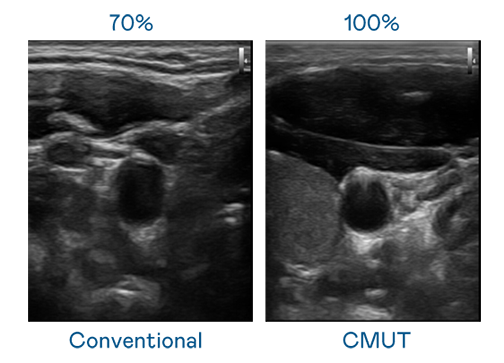

CMUT 技术是一种用电容式微机电元件来产生超音波讯号的技术。与传统 PZT 压电式技术相比,CMUT 频宽增加 30%,更宽频的超音波讯号让影像解析度大幅提升,是实现高影像品质医疗超音波扫描、促进精准医疗发展的关键技术。

超音波影像的解析度高低,首先取决于探头能发出的讯号频宽。j9九游会真人国际第一 CMUT 可提供高清晰的超音波讯号,提供高频宽、高灵敏度、影像纹理细节更高的超音波影像,协助医护人员缩短影像判读时间及利用精准的医疗影像进行诊断。